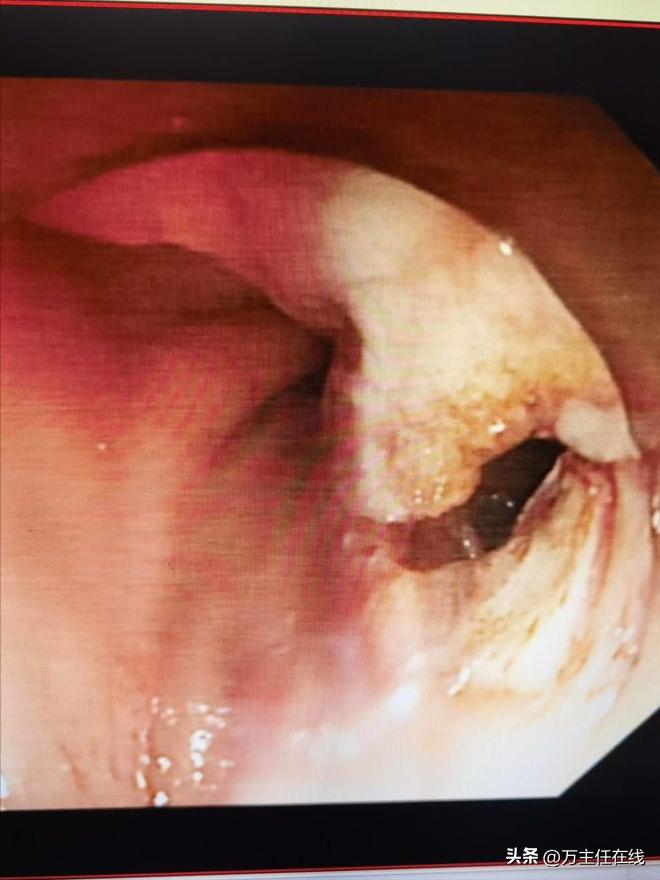

术前内镜探查见胃腔内多发瘘口形成并有少量粘液自腹腔瘘入

胃窦后壁受压,胃腔梗阻;超声内镜引导下胃窦后壁穿刺避开肠管及重要血管留置导丝于腹腔

胃窦后壁穿刺点以囊肿切开刀扩大穿刺通道,并有粘液流入胃腔

有粘液流入胃腔